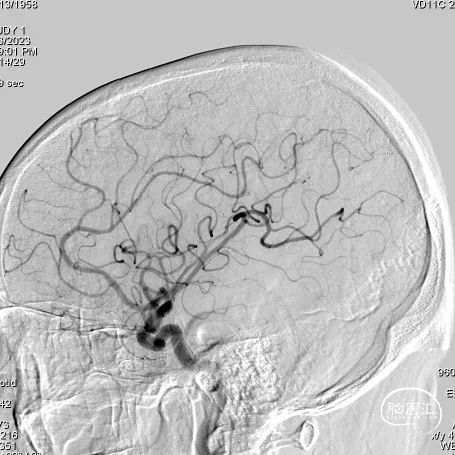

左侧颈内动脉造影

① 右侧椎动脉V4段夹层动脉瘤伴血栓形成;

② 双侧额叶、侧脑室旁多发腔隙性梗塞及缺血灶;

③ 双侧筛窦、上颌窦炎。

长鞘到位后工作角度造影;尽量暴露双椎汇合部,方便术中判断支架头端锚定位置。

造影提示YonFlow®血流导向密网支架头端和后半段打开良好。

术后造影。

蒙片提示支架展开良好。

术后半年复查造影:YonFlow®血流导向密网支架贴壁良好,载流动脉前向血流良好。